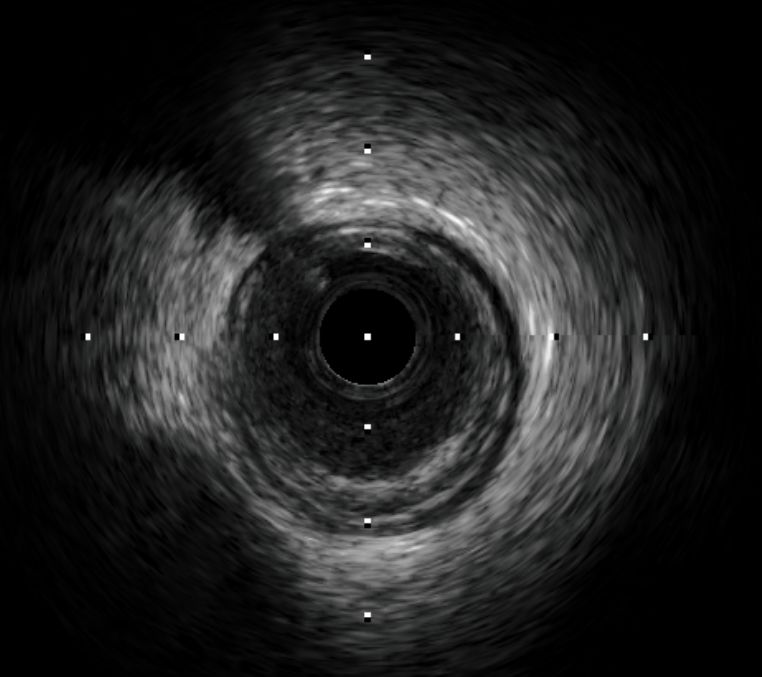

与自然图像相比,医学图像的内容和信息密度通常较低,因此医学影像的结构相对固定,语义信息也较为简单。常见的医学影像类型,比如CT、MRI、超声、病理切片和OCT等等,大多数成像方式对单一的人体器官进行成像时得到的影像结构都会相对固定一些。比如说下图的血管内超声影像,其图像特点就是官腔(lumen)的位置相较于整幅图而言永远都处于中心位置。

血管内超声图像(IVUS)